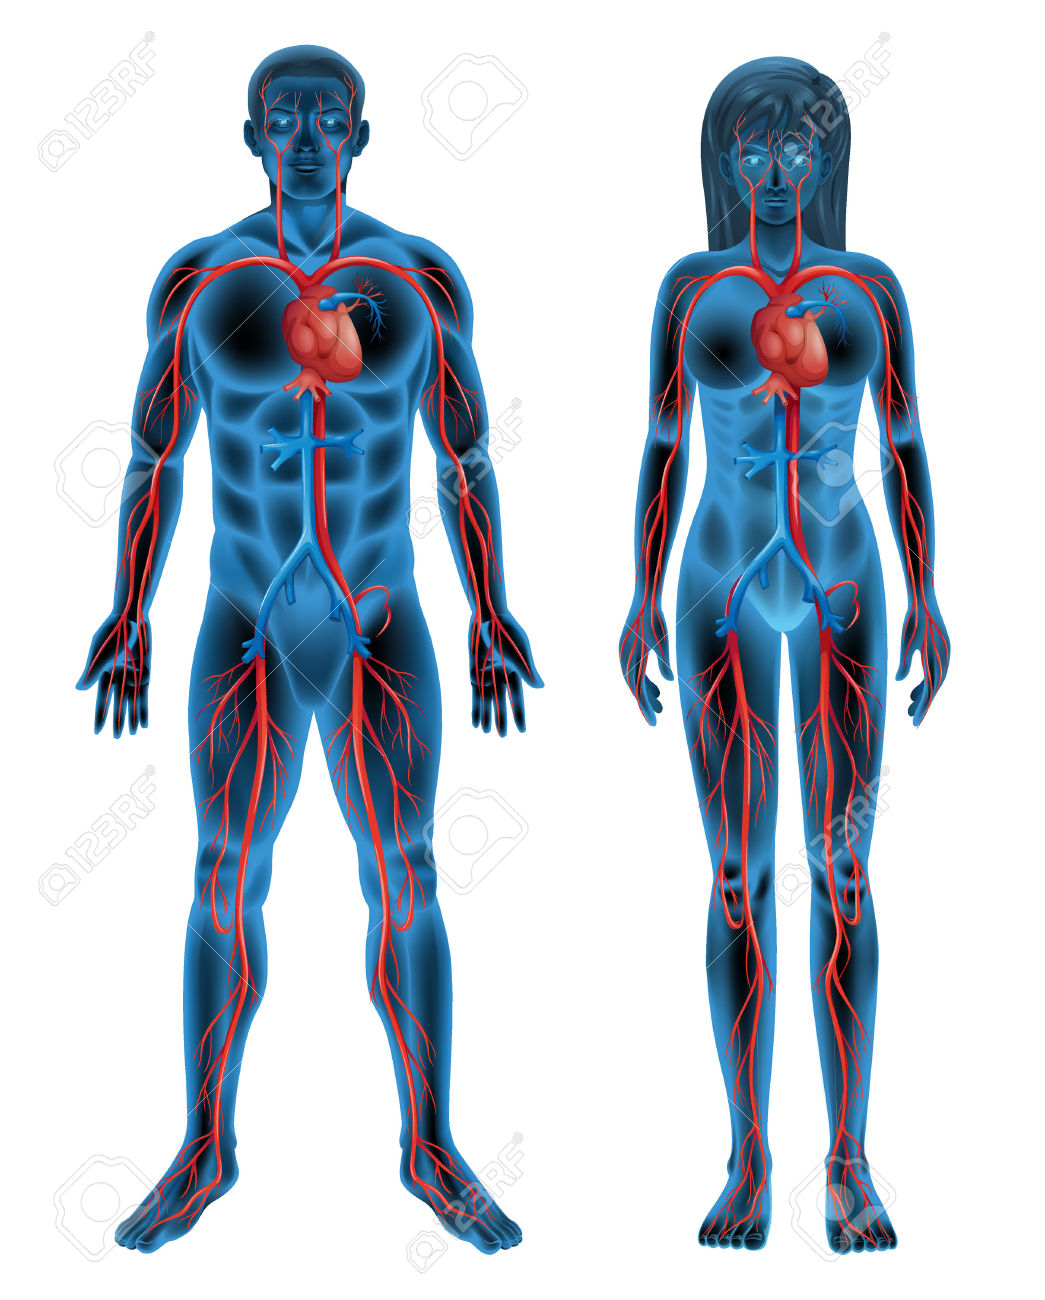

6. The Circulatory System (human)

- Components of blood and their functions (Red blood cell, white blood cell, platelets and plasma (blood groups)

- Blood vessels (arteries, veins, and capillaries)

- The heart (structure and function)